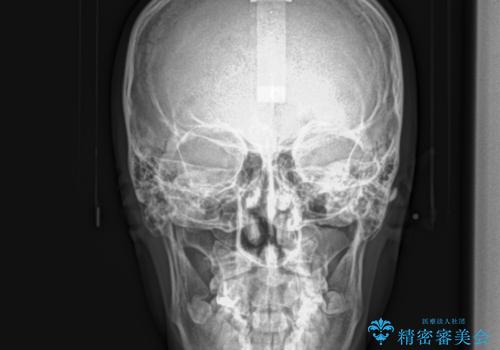

ガタガタの歯並び、八重歯をなおしたい、骨格性下顎前突 カモフラージュ矯正

骨格的に上顎骨が小さいために相対的に下顎骨が前に出ていたため、歯の傾きなど理想的な仕上がりが難しく、外科矯正ではなく歯列矯正の場合はカモフラージュ矯正になること説明の上、矯正治療を進めることになりました。